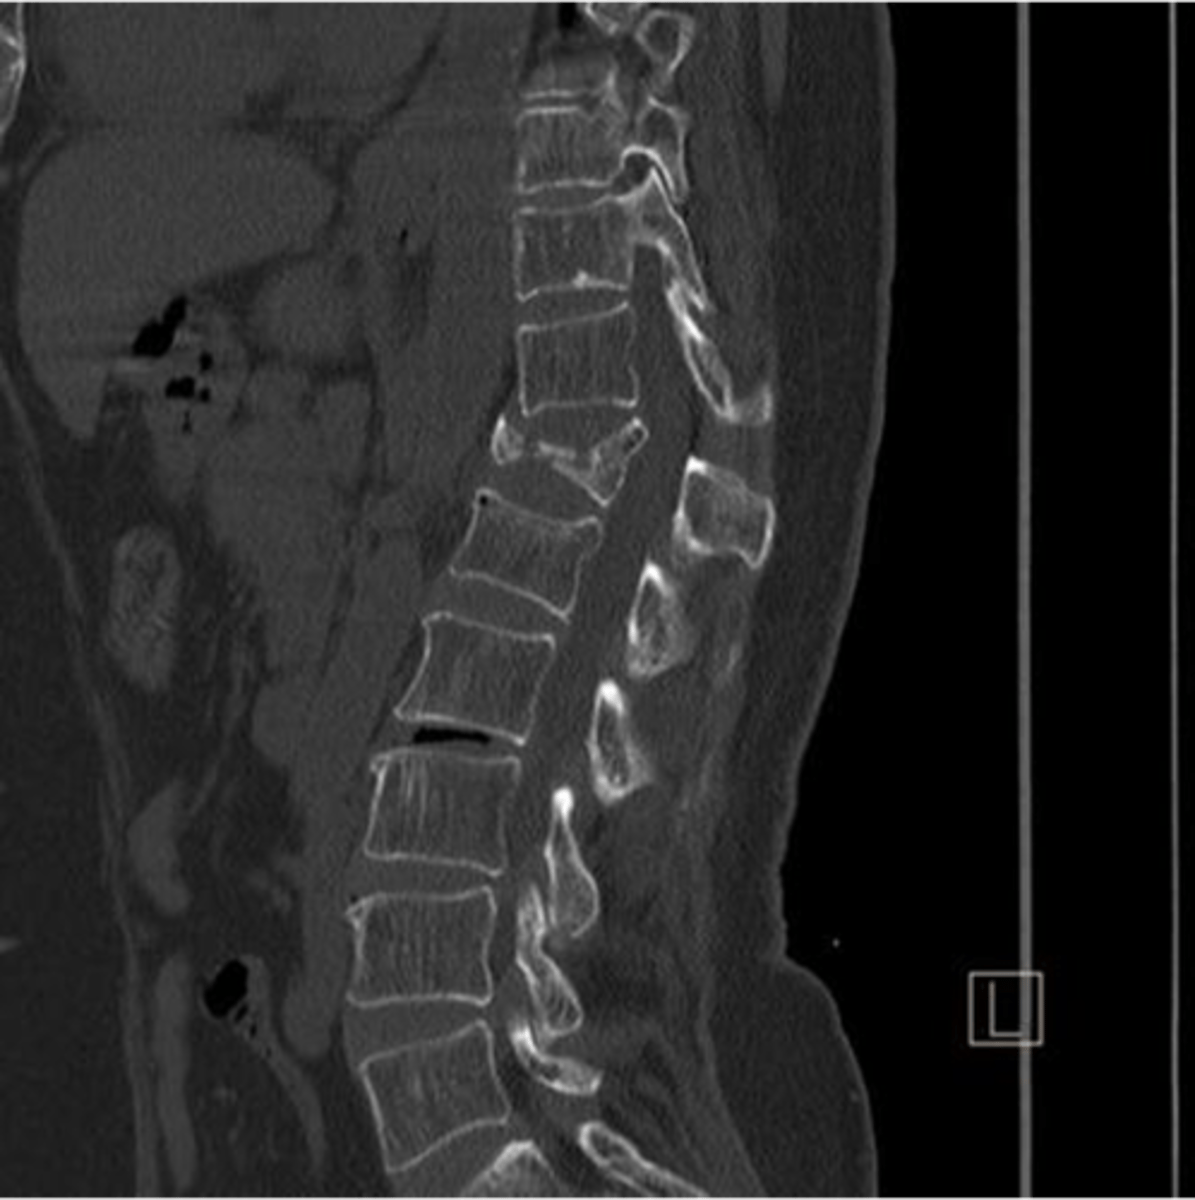

CT myelography can be used to evaluate the ____ and _____

spinal cord and canal

CT myelography is a good alternative to MRI to identify

spinal stenosis, disc herniation, spondylosis, arthritis

plain radiography of the head/neck is good to determine

flexion and extension of the spine (evals stability)

herniated disc disease

spinal compression fracture

cervical burst fracture

spondylosis

arthritic degeneration of the spine

spondylosis is generally accompanied by ____ formation and disc ______

osteophyte formation and disc thinning/collapse

spinal stenosis

Narrowing of the spinal canal that causes pressure on the spinal cord (nerves)

spinal stenosis etiology

osteophytes, disc herniation, tumors, trauma